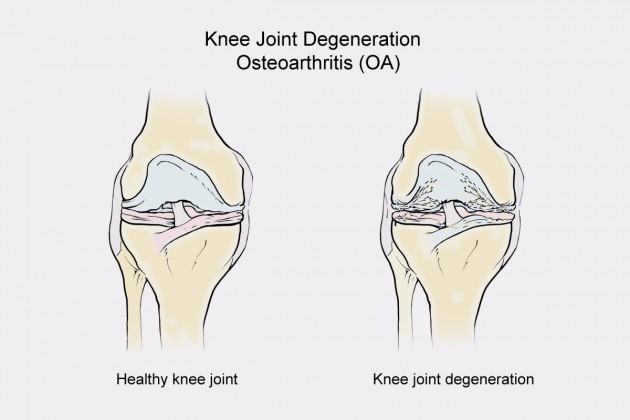

Joints degeneration called osteoarthritis (OA) is common in the modern society. The reason is obesity, lack of physical activity or repetitive stressed daily activities. In Western countries almost 20% population suffers from this condition.

Osteoarthritis can be present in every kind of the joints where the hyaline cartilage occurs. Usually this condition is connected with knee or hip joint. Obesity in 20-25 years old patients can cause OA after early 50. The problem is serious because the disease affects muscles, joints capsules, ligaments, joint surfaces and neighbouring joints.

In OA treatment is used pharmacotherapy, physical therapy, losing the weight and using orthopaedic medical braces.